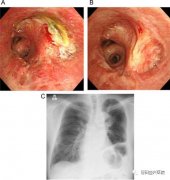

支氣管鏡檢查是將細(xì)長的支氣管鏡經(jīng)口或鼻置入患者的下呼吸道,即經(jīng)過聲門進(jìn)入氣管和支氣管以及更遠(yuǎn)端,直接觀察氣管和支氣管的病變,并根據(jù)病變進(jìn)行相應(yīng)的檢查和治療。廣義上包括經(jīng)支氣管鏡病灶活檢、支氣管粘膜活檢、經(jīng)支氣管鏡透壁肺活檢(Transbronchial LungBiopsy,……